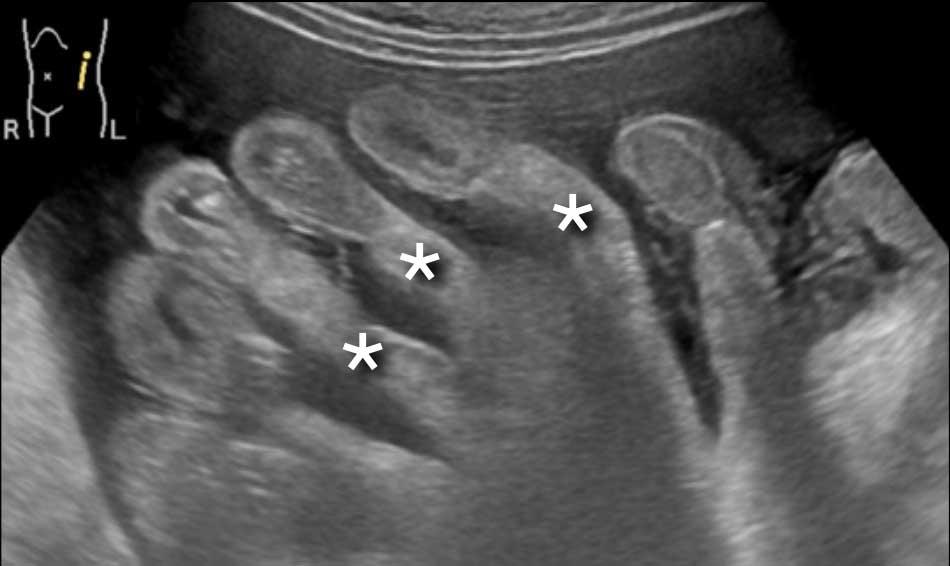

Hình ảnh

Có một lượng nhỏ dịch cổ trướng.

Mạc treo ruột dày được quan sát thấy bám vào đoạn cuối của ruột non, hình ảnh điển hình của tổn thương xâm lấn mạc treo.

Hình ảnh này thuộc về một bệnh nhân khác nhập viện với cổ trướng.

Mạc treo ruột dày (dấu hoa thị) được quan sát thấy bám vào đoạn cuối của ruột non.

Đây là hình ảnh điển hình của tổn thương xâm lấn mạc treo trong ung thư phúc mạc.